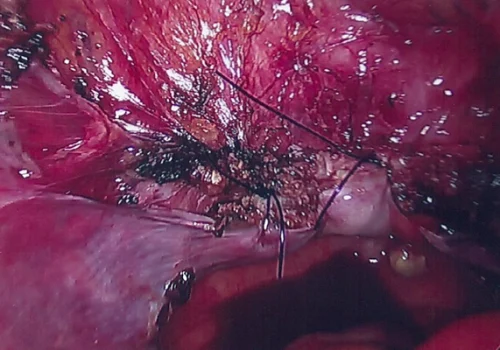

Procedure

She subsequently underwent Total Laparoscopic Hysterectomy and removal of both Tubes and Ovaries.